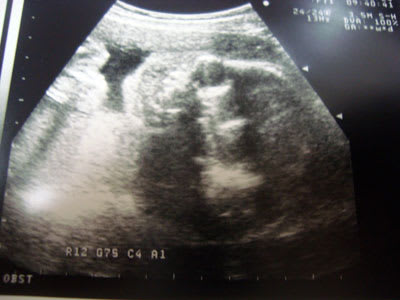

でも、朝からお腹の我が子の検診が予定されています。

『今日は、先週の検査結果を聞くだけだから、超音波見ない日だよ』って。

のっちょの名前が呼ばれ、病室に入り・・

お腹を見る為、ベットに横になったのっちょのお腹に、超音波の器具を当て始めると、もう~大変。

さて、昨日の問題の答えです。

我が家の第二子の性別は・・わかりませんでした(笑)

丁度、お股を閉じちゃっているみたいで、先生がお腹とかを叩いて、体勢を変えようとしてくれたんですが・・ダメだった。

大事な部分をお披露目してはくれませんでした。

でもね、我が子は順調です♪